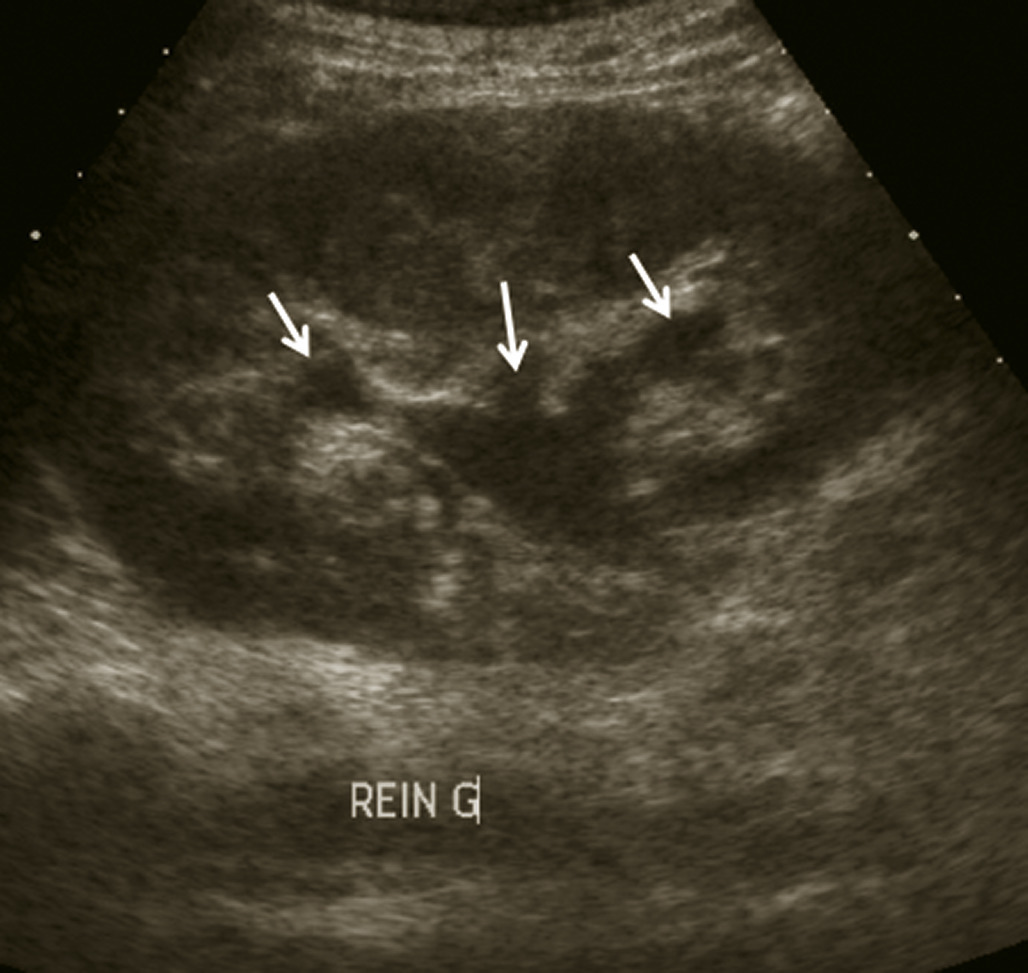

L’échographie abdominale a l’inconvénient d’être opérateur-­dépendante. Ses principales indications sont la lithiase biliaire et ses complications, des douleurs abdominales chez les patients minces et surtout chez la femme pour rechercher une pathologie gynécologique en utilisant le cas échéant des sondes endocavitaires. Ainsi, l’échographie est utile pour affirmer la lithiase biliaire et la cholécystite aiguë (fig. 1) ou objectiver une dilatation de la voie biliaire principale (VBP), rechercher une urétéro-hydronéphrose et des signes indirects en cas de colique néphrétique (fig. 2 et 3), débrouiller le diagnostic des douleurs abdomino-­pelviennes chez la femme.

L’échographie est essentielle, montrant un épaississement de la paroi vésiculaire à plus de 6 mm et la présence de calcul(s) ou « sludge » (fig. 1), sans dilatation de la voie biliaire principale (VBP). La complication principale est la péritonite et le choc septique souvent sur une gangrène de la paroi vésiculaire qui peut conduire de manière exceptionnelle vers le cholépéritoine.

L’échographie peut montrer une discrète asymétrie des cavités excrétrices rénales, voire l’obstacle lithiasique avec dilatation d’amont (fig. 2 et 3). L’uroscanner complète le bilan et localise si besoin le calcul. Outre le traitement de la cause (calcul, compression extrinsèque…), le traitement antalgique est primordial : anti-inflammatoires non stéroïdiens (AINS), paracétamol, anti­spasmodiques voire dérivés morphiniques. On procédera à la pose d’une sonde urétérale en cas d’anurie (rein unique), de fièvre sur rétention du haut appareil ou de crise hyperalgique.